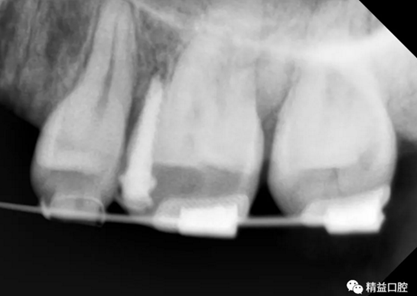

矯正前全口曲斷片

從片子上可以清除看到,上牙門牙牙根吸收非常厲害。